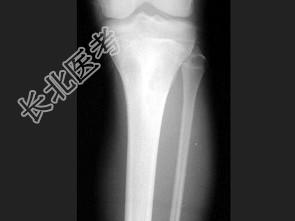

- 单项选择题男,22岁, 膝部酸痛、肿胀,结合图像, 最可能的诊断是 ( )

A、纤维性骨皮质缺损

B、嗜酸性肉芽肿

C、非骨化性纤维瘤

D、软骨黏液样纤维瘤

E、骨样骨瘤